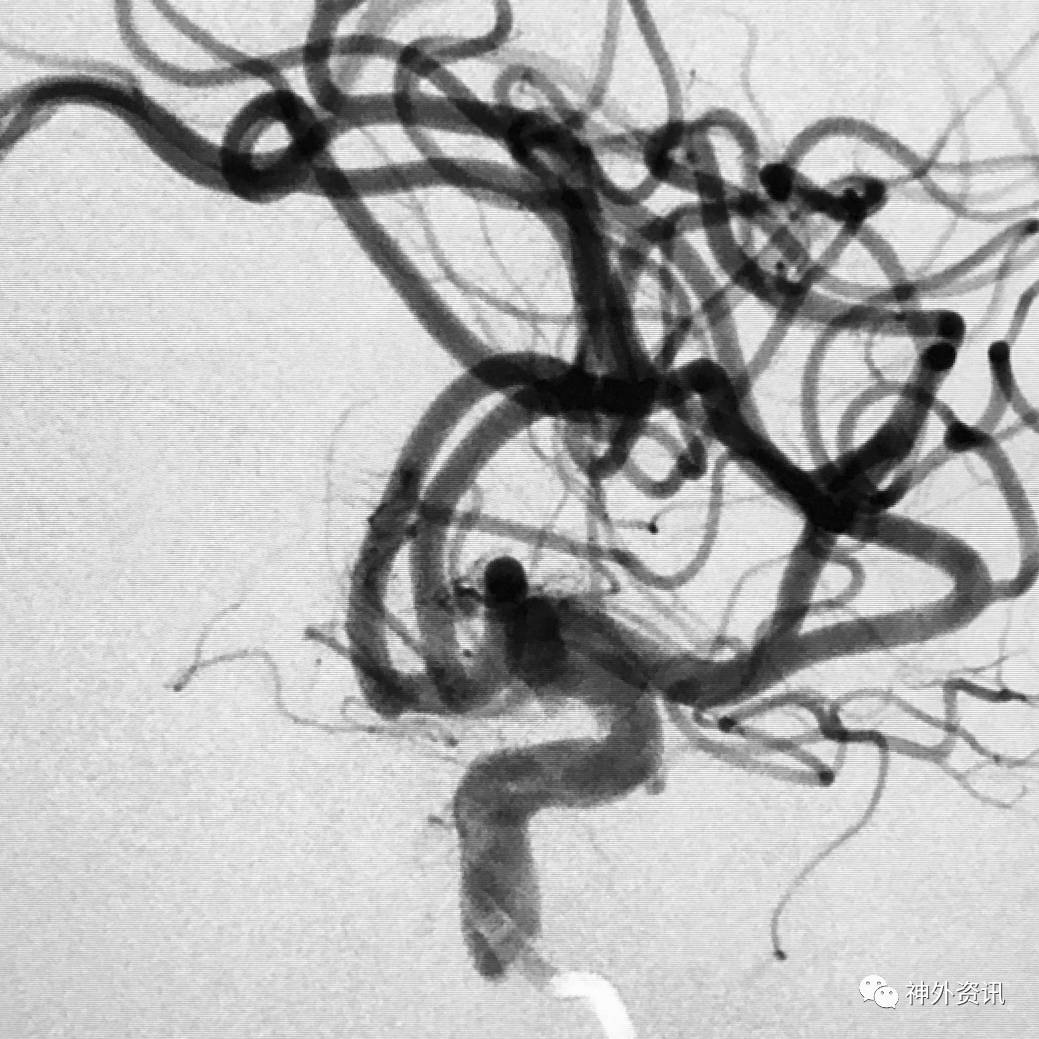

病例一